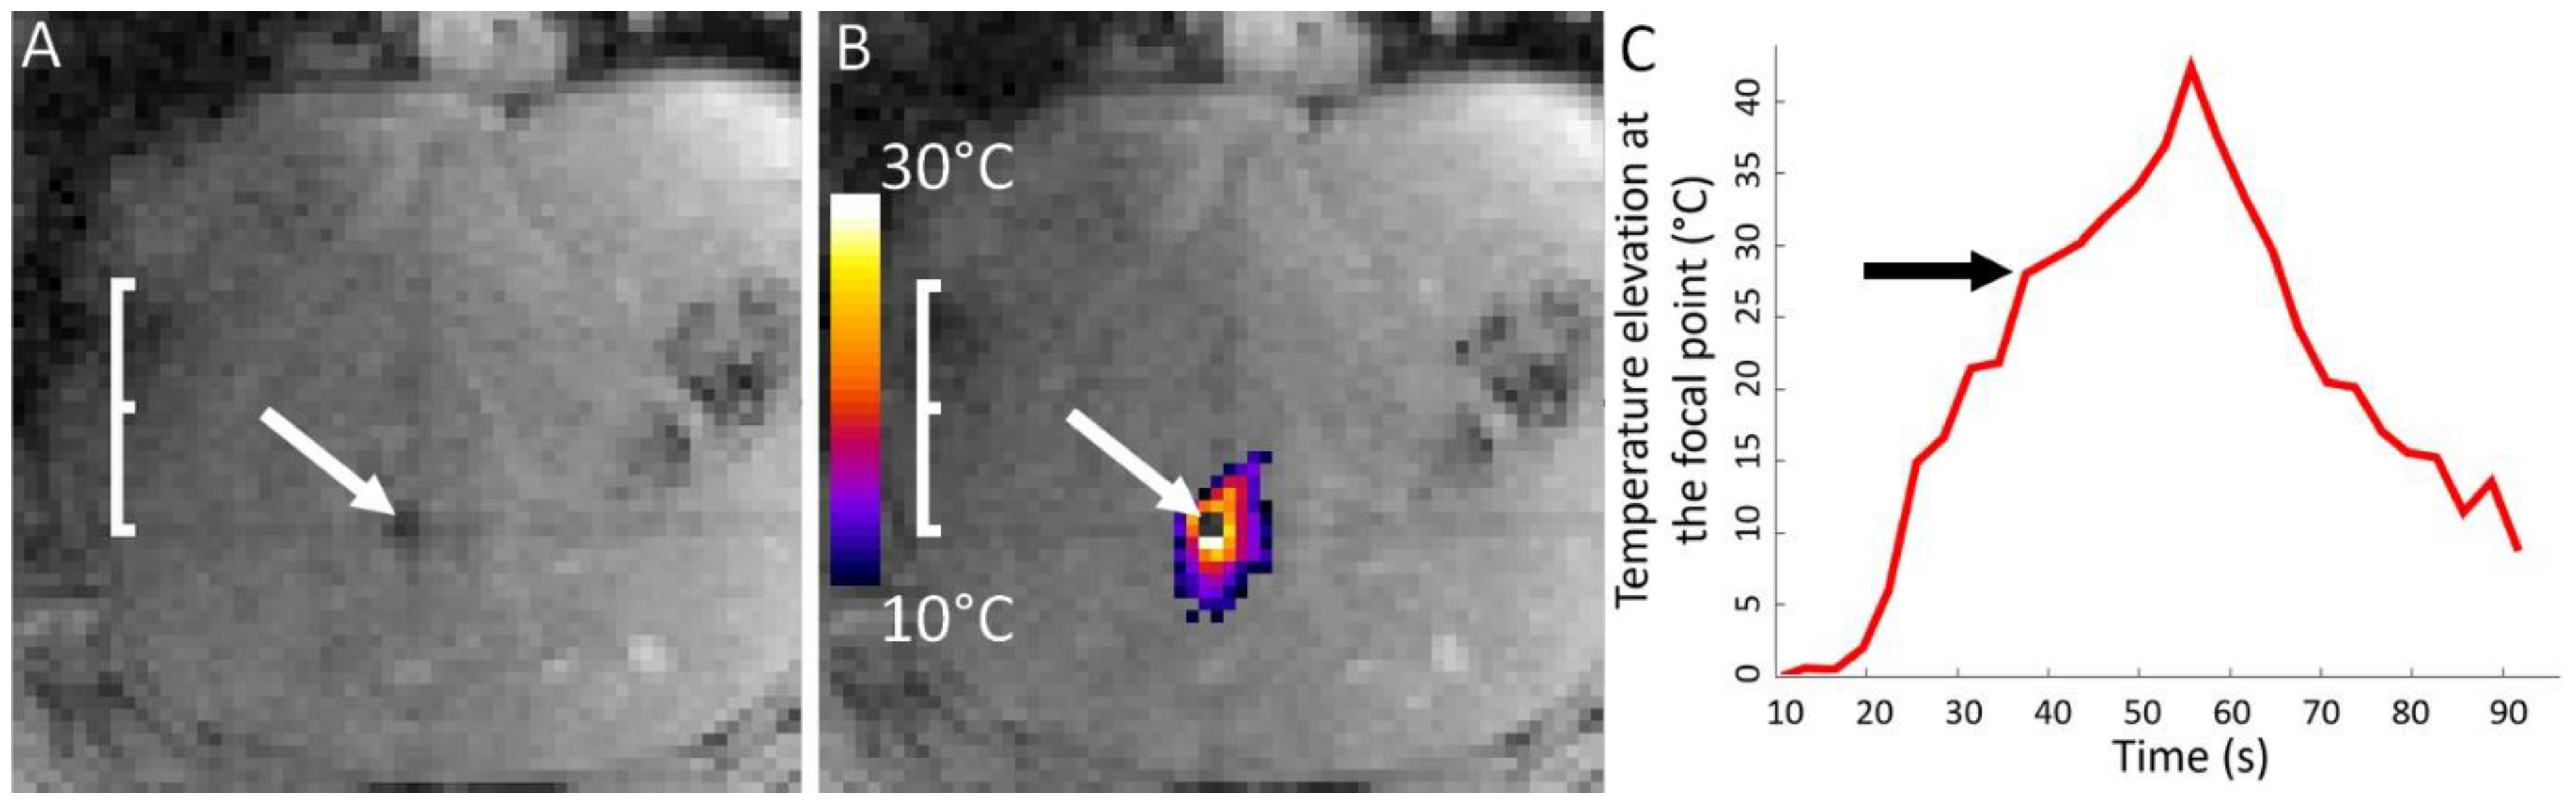

| Pig | RF Ablation Size (mm3), from MR Images (along AP, LR and HF Axes) | Temperature Reached During HIFU Ablation (°C) | HIFU Ablation Longest Axis (mm) from MR Images; See Figure 6 and Figure 7 | HIFU Ablation Longest Axis (mm), from Gross Pathology; See Figure 6 and Figure 7 | Planned Center-to-Center Distance between the RF and MRgHIFU Ablations (mm), from MR Images | Center-to-Center Distance between the RF and MRgHIFU Ablations (mm), from Gross Pathology | Center-to-Center Distance between the RF and MRgHIFU Ablations (mm), from MR Images | Near-Field Side Effects Grade |

|---|---|---|---|---|---|---|---|---|

| 1 | 4.9 × 6.1 × 4.8 | 63 | - | - | 0 | - | - | 1a |

| 2 | 7.2 × 6.3 × 9.2 | 86 | 6.9 | - | 11.8 | - | 10.1 | 1a |

| 3 | 4.6 × 3.7 × 4.5 | 85 | 15.8 | 16.5 | 6.7 | 3.6 | 3.2 | 1a |

| 4 | 6.7 × 6.1 × 6.8 | 86 | 7.4 | 7.9 | 16.1 | 16.0 | 16.2 | 1a |

| 5 | 5.1 × 4.7 × 6.2 | 62 | 21.1 | 23.2 | 18.4 | 24.2 | 24.1 | 1a |

| 6 | 3.0 × 4.6 × 5.5 | 58 | 14.0 | 15.0 | 11.2 | 10.3 | 10.3 | 1b |